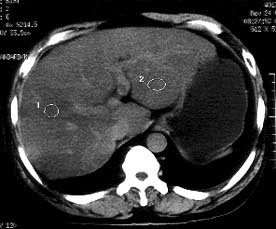

男性,53岁,腹痛、腹泻3天。体检:肝大,达肋下5cm,质中,无压痛。

ct平扫:肝脏密度普遍不均匀减低,ct值6-18hu,肝内血管相对显示为高密度。

ct诊断:脂肪肝。